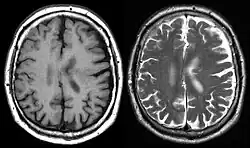

Die Diagnose kann nachgeburtlich mittels Ultraschall gestellt werden, die Magnetresonanztomografie kann hilfreich sein, um das Vorliegen anderer Gyrierungsstörungen zu überprüfen.